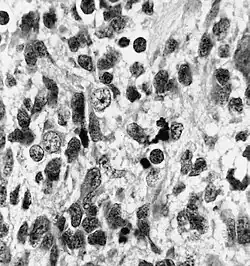

Nabłoniak rdzeniakowy (łac. medulloepithelioma, ang. medulloepithelioma) – nowotworowy guz mózgu pochodzenia zarodkowego. Jest guzem o wysokiej złośliwości (IV° według WHO). Występuje u dzieci, przed 5. rokiem życia, najczęściej w okresie niemowlęcym, niekiedy jako guz wrodzony.